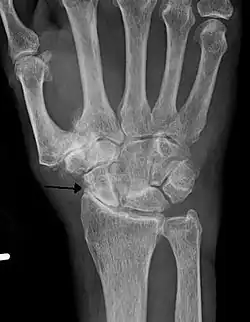

-

Severe osteoarthritis and osteopenia of the carpal joint and 1st carpometacarpal joint